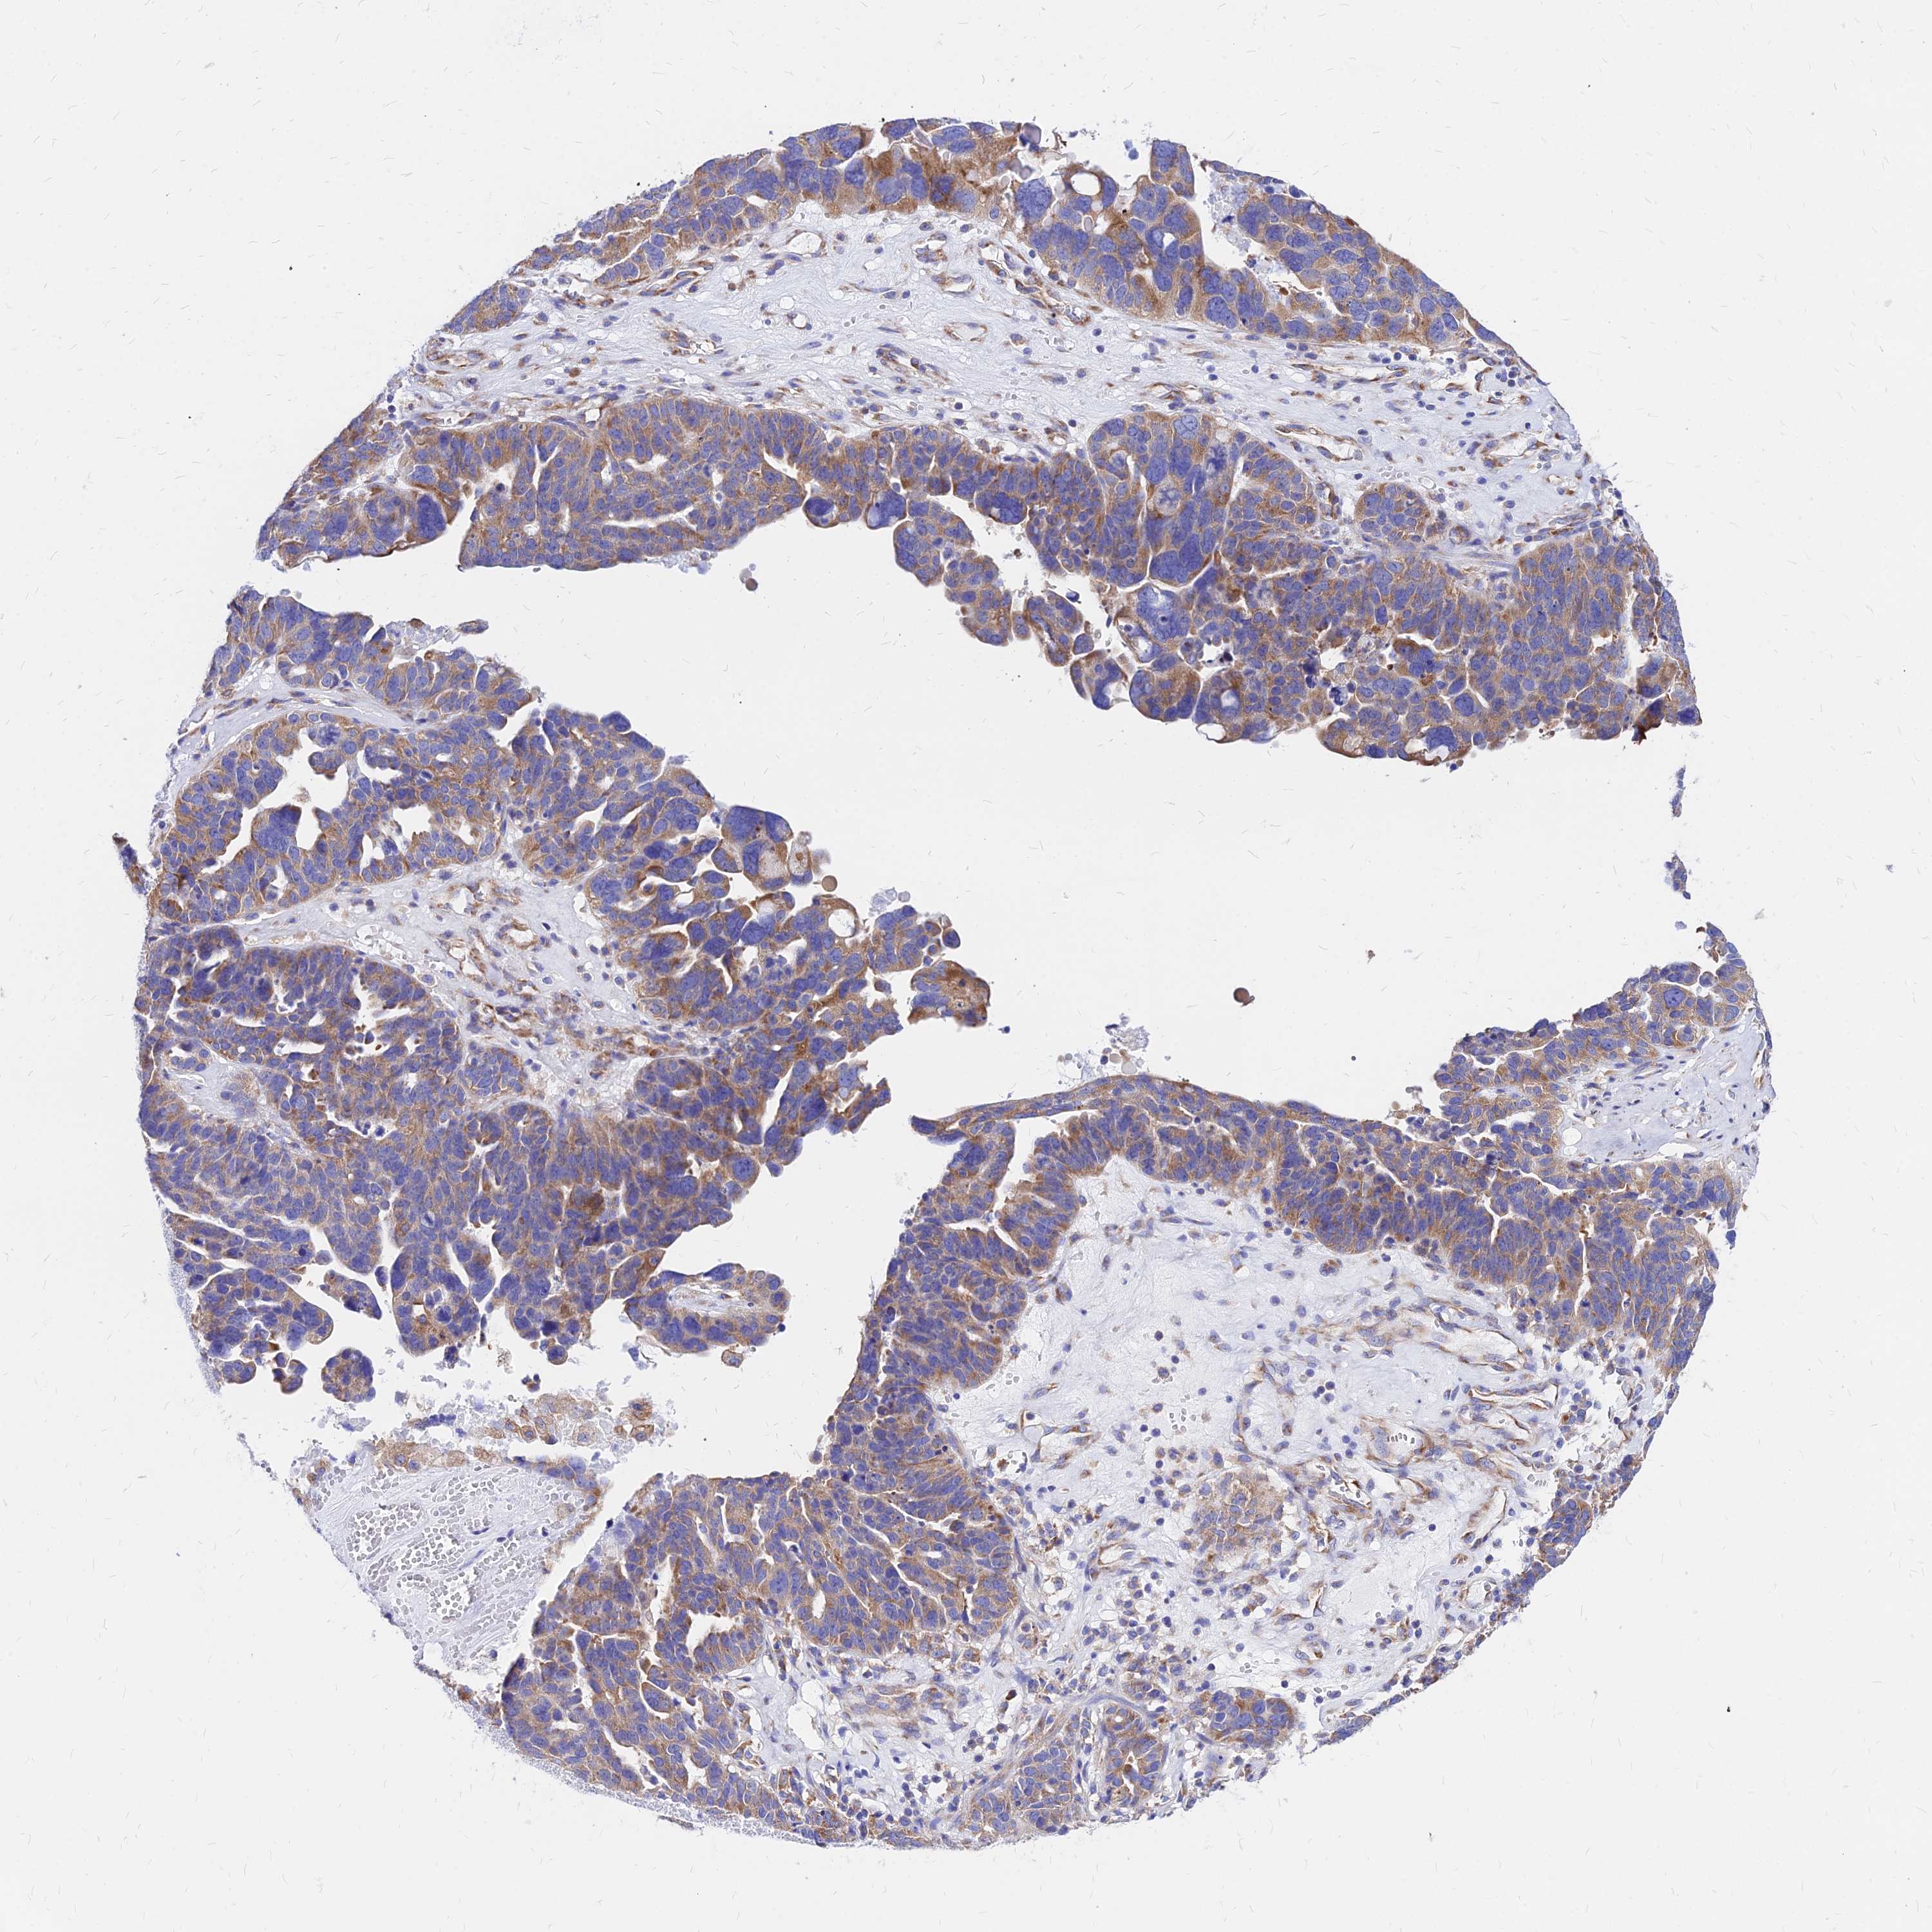

OVARIAN CANCER - Protein expressioni

A mouse-over function shows sample information and annotation data. Click on an image to view it in a full screen mode. Samples can be filtered based on level of antibody staining by selecting one or several of the following categories: high, medium, low and not detected. The assay and annotation is described here.

Note that samples used for immunohistochemistry by the Human Protein Atlas do not correspond to samples in the TCGA dataset.

Antibody stainingi

Antibody staining in the annotated cell types in the current human tissue is reported as not detected, low, medium, or high, based on conventional immunohistochemistry profiling in selected tissues. This score is based on the combination of the staining intensity and fraction of stained cells.

Each image is clickable and will lead to virtual microscopy that enables deeper exploration of all samples and also displays staining intensity scores, fraction scores and subcellular localization as well as patient and tissue information for each sample.

Antibody HPA043014

Staining

High

Medium

Low

Not detected

Intensity

Strong

Moderate

Weak

Negative

Quantity

>75%

75%-25%

<25%

None

Location

Nuclear

Cytoplasmic/membranous

Cytoplasmic/membranous,nuclear

Cystadenocarcinoma, serous, NOS

Carcinoma, NOS

Cystadenocarcinoma, mucinous, NOS

Carcinoma, endometroid